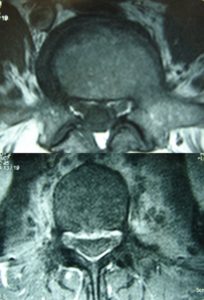

Μαγνητική Τομογραφία της Ο.Μ.Σ.Σ. (13/06/2007) Ακολουθία Τ1 και Τ2

Οβελιαία τομή (α,β) Παρατηρείται η ύπαρξη Επισκληριδίου Αποστήματος στο επίπεδο Ο3-Ο4 που προκαλεί μεγάλη στένωση του σπονδυλικού σωλήνα, με απώθηση του νωτιαίου σάκου. Διαπιστώνεται επίσης η ύπαρξη παρα-σπονδυλικού αποστήματος

Εγκαρσία τομή (γ,δ) Παρατηρείται η ύπαρξη Επισκληριδίου όπως επίσης και προ-παρασπονδυλικού αποστήματος.